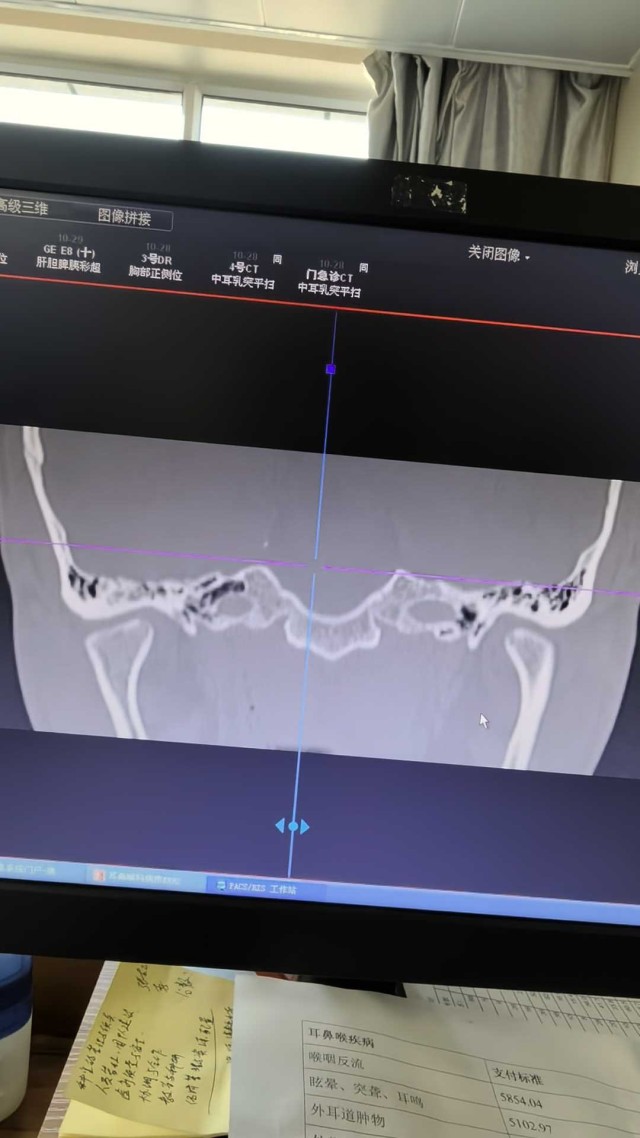

中耳胆脂瘤?外耳道胆脂瘤?

如水方能行远耳科医师

病例信息患者,男,19岁,主诉:右耳听力下降伴耳闷2月入院。半月前因右耳流脓入我院行抗感染治疗,干耳半月,现患者欲行手术治疗。病例讨论一月前感染流脓耳镜照片干耳后耳镜图片该患者是外耳道胆脂瘤还是中耳胆脂瘤,因外耳道有肉芽通过耳镜无法判断,CT见盾板有破坏,砧蹬关节附近有病变,手术方式怎么选择?